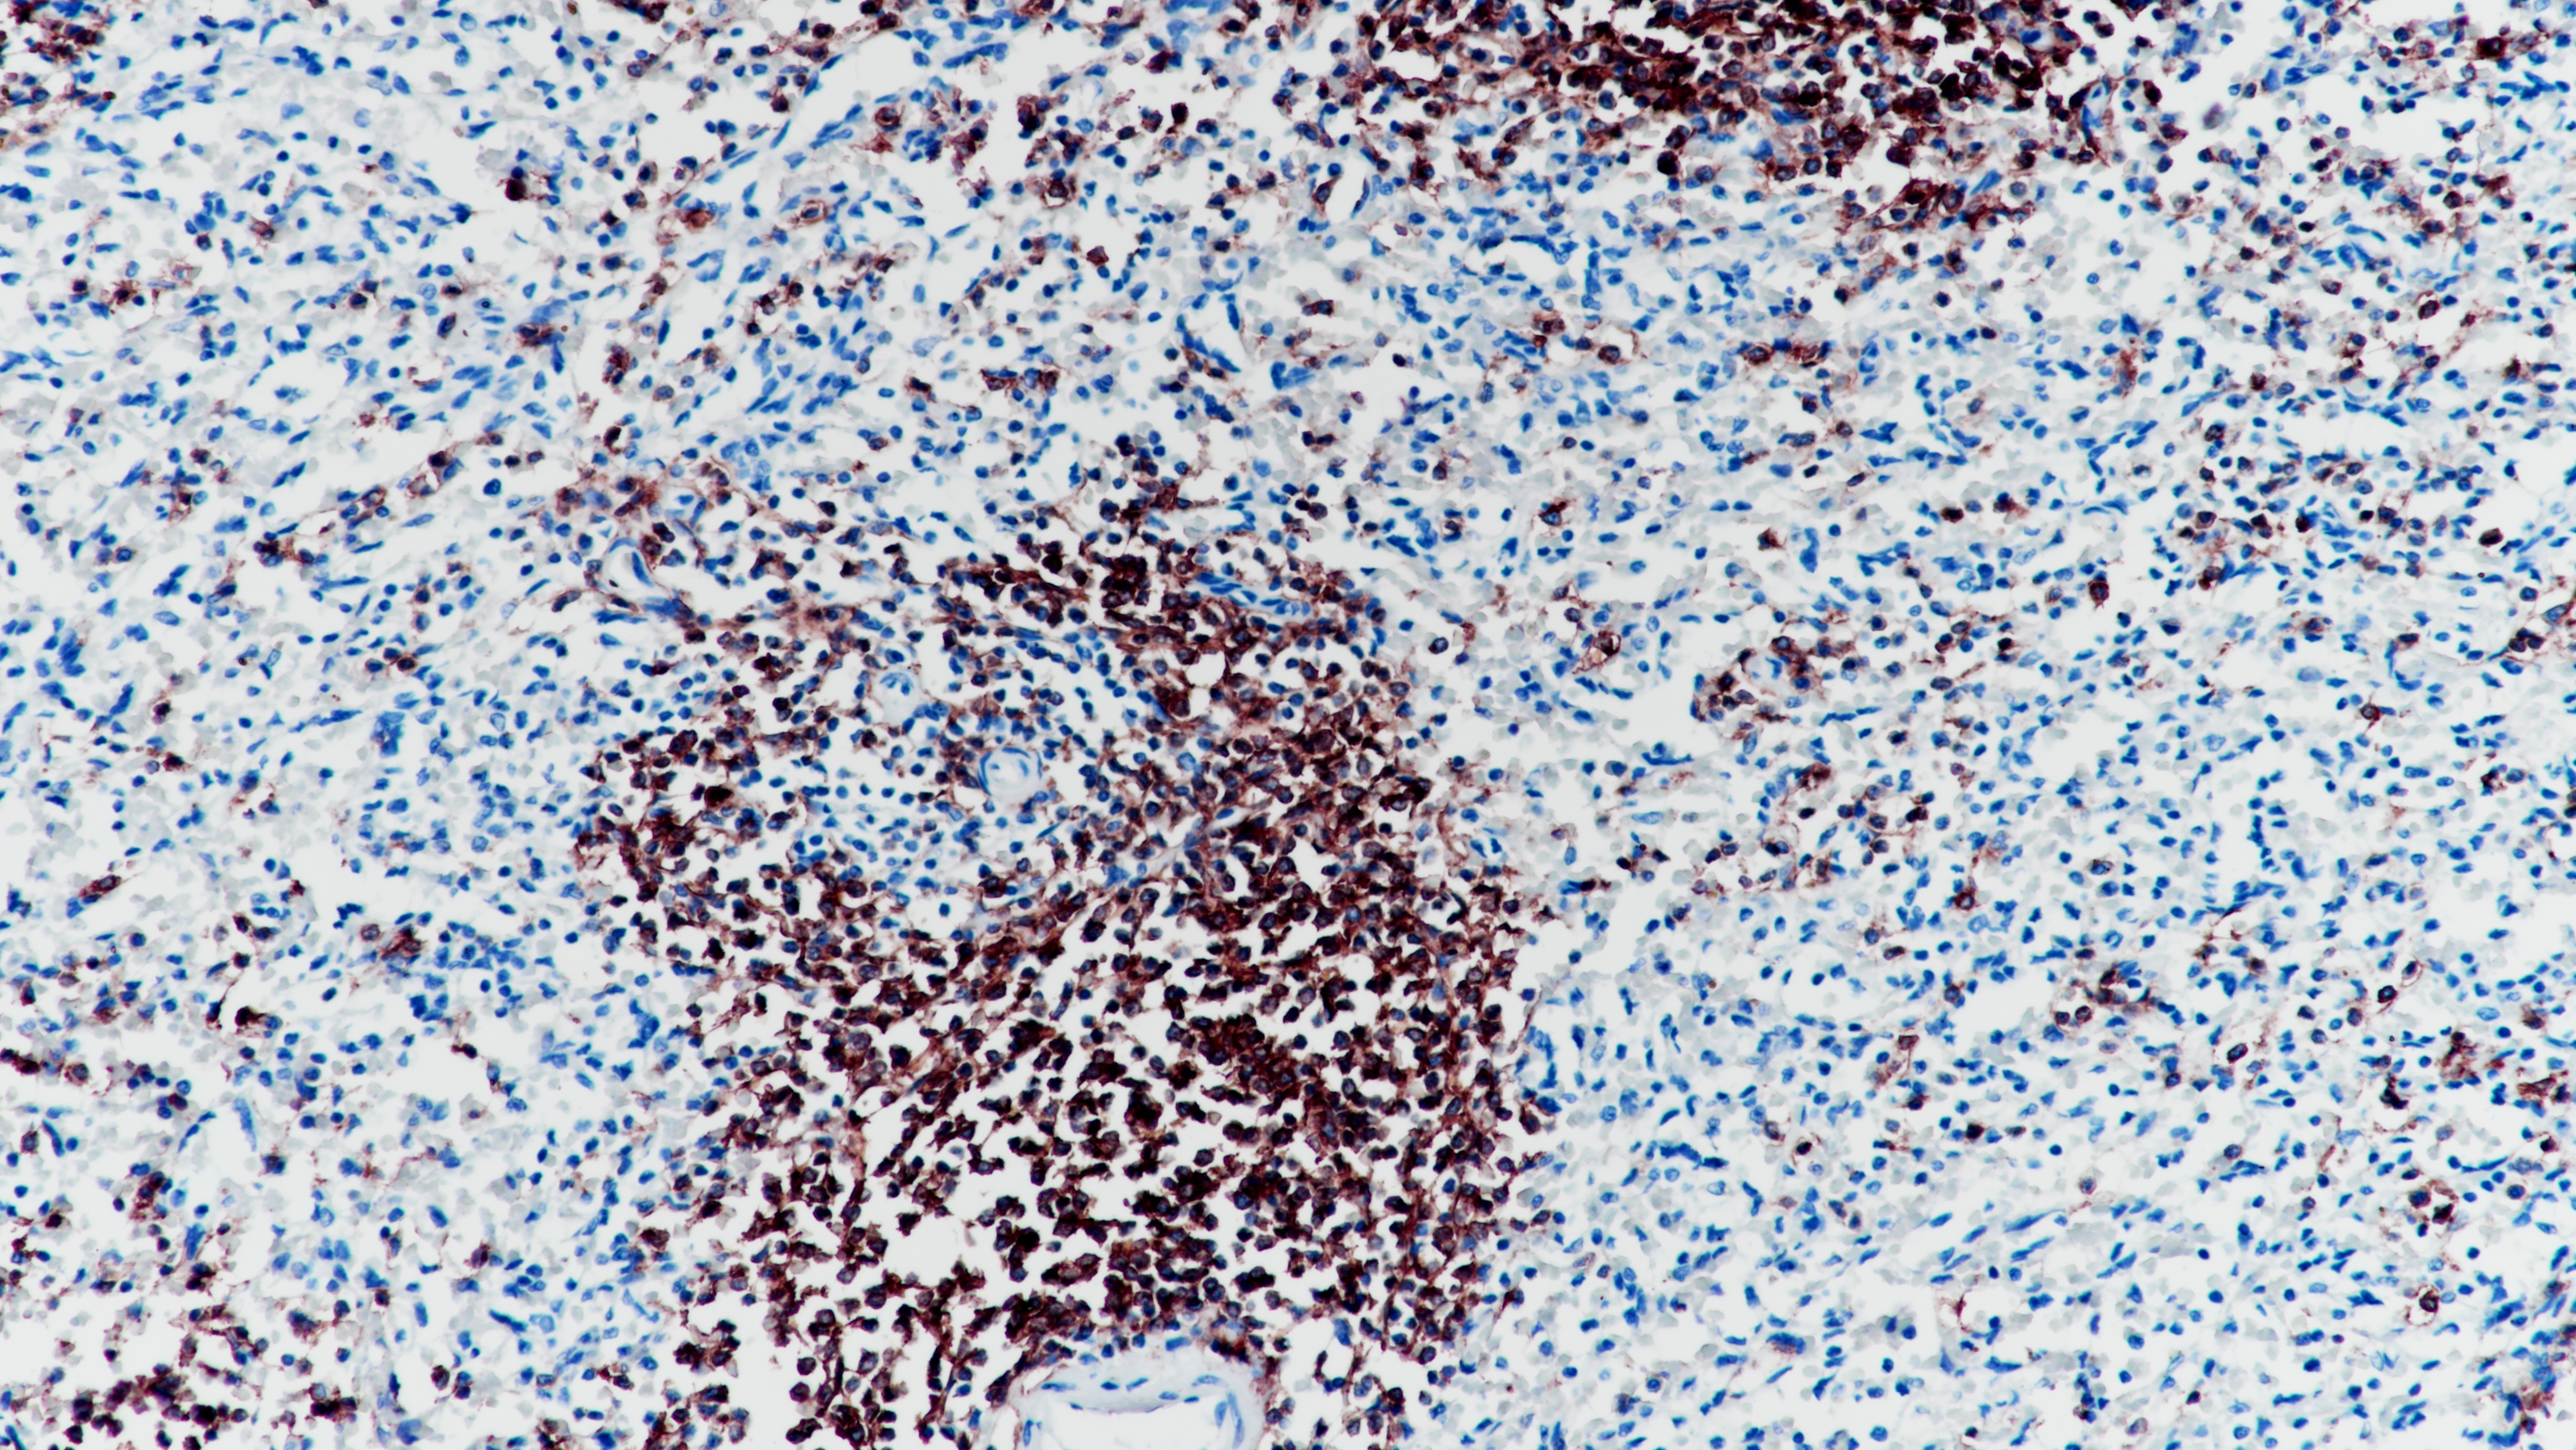

1..Danfei Xu,Fengzhi Feng,Yuqing Pei,Yujuan Zhang,Yue Wu,Yi Guo,Wei Cui. Differential expression of SALL4 in CTCs derived from hydatidiform moles and gestational trophoblastic neoplasms[J].

2..American Journal of Reproductive Immunology,2020,83(5).